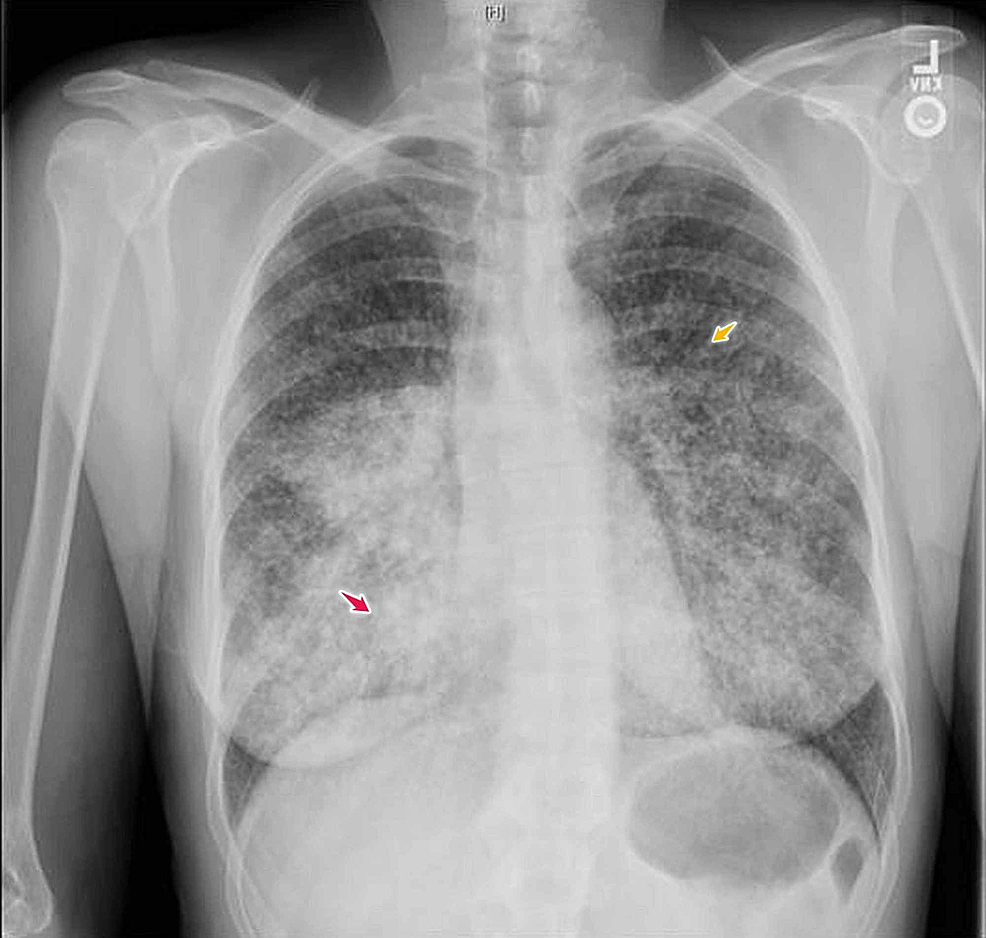

Cureus Adenocarcinoma Of The Lung Presenting With Intrapulmonary

Imgs For Chest X Ray Abnormal

Imgs For Chest X Ray Abnormal